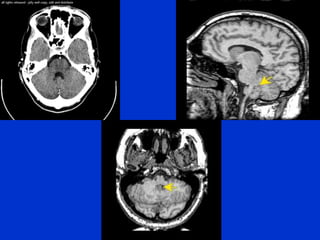

The document provides an overview of normal brain anatomy including key structures like the central sulcus, lateral sulcus, white matter tracts, brain stem, ventricular system, and basal cisterns. It was authored by Dr. Maliha Fansur, Assistant Professor at SIMS/SHL, who appears to have expertise in neuroanatomy.